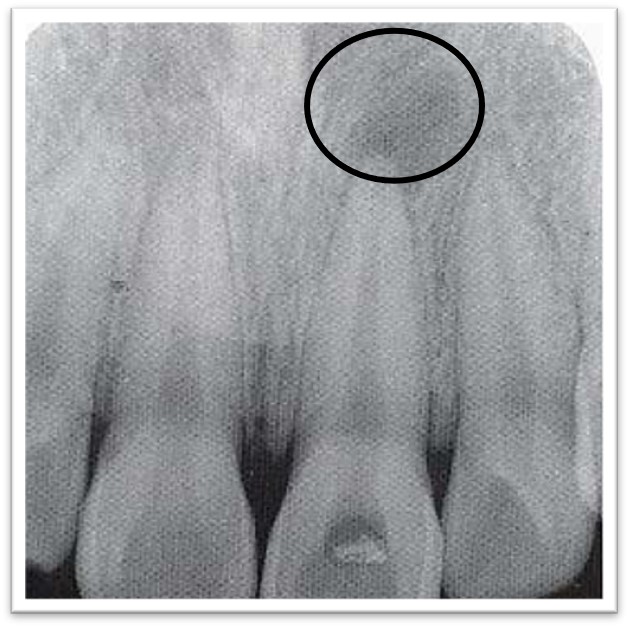

2. X线:根尖区牙周间隙增宽,或界限清楚的圆形透射影(图9.2-1)。

图9.2-1 根尖周肉芽肿X线